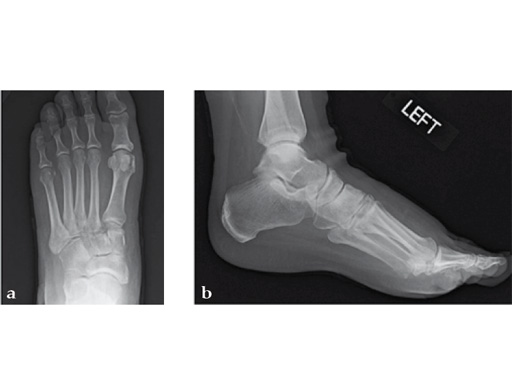

Case 7: VA -locking X-plate

A 49-year-old woman had extreme pain in the talonavicular joint.

Case provided by Andrew Sands, New York, New York, USA

As isolated fusion of the talonavicular joint is often hard to achieve, a 4.0 mm lag screw a plus X-plate was used (see Fig. 2a-c).